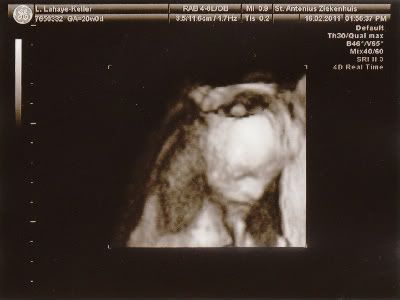

We hebben vandaag de 20 weken echo gehad en alles is in orde met de kleine!

Moet nog wel een keer terug volgende week, want ze kon niet alles goed zien maar de belangrijkste dingen waren helemaal in orde! Ben echt opgelucht... Hieronder wat echo foto's.